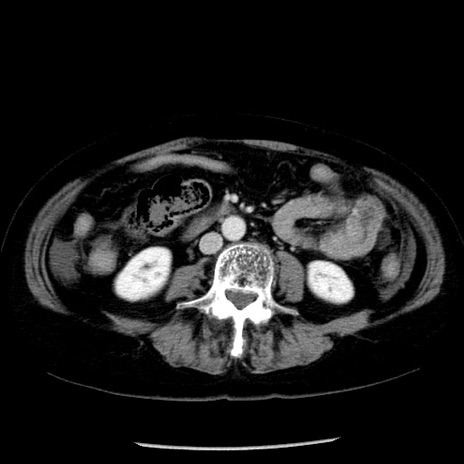

症例13(横断像)

【症例】70歳代女性

【主訴】腹痛、嘔吐

【現病歴】15時間程前(昨晩)より腹痛あり。今朝になっても症状の改善なく、嘔吐あり。腹痛も増悪あり、救急外来受診。

【既往歴】子宮癌全摘術後

【身体所見】意識清明、BP 121/72mmHg、P 74bpm、SpO2 100%(RA)、腹部:平坦・軟、腸雑音ほぼ聴取せず。下腹部・心窩部・臍左上に圧痛あり。反跳痛なし。

【データ】WBC 10600、CRP 0.15